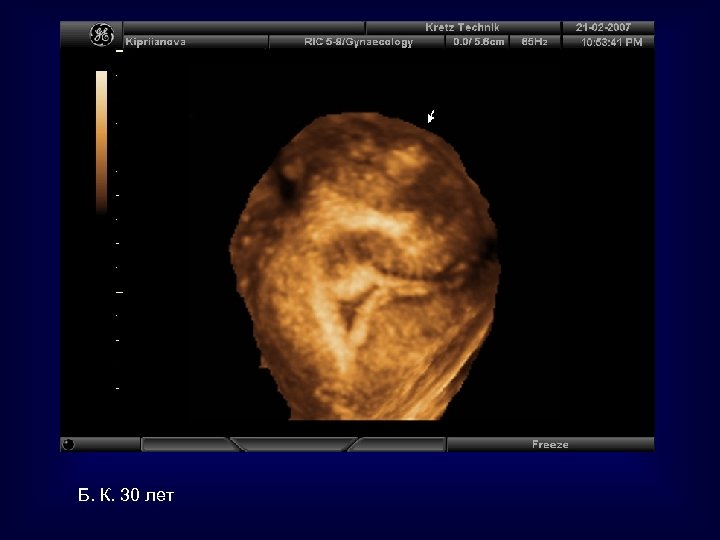

Б. К. 30 лет